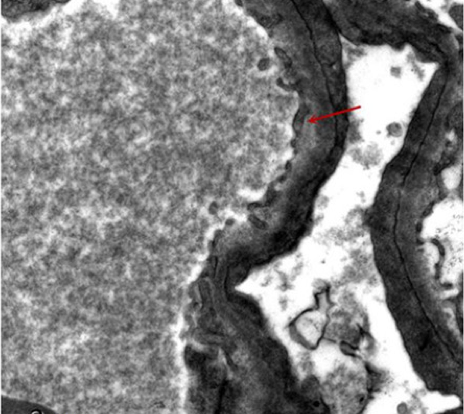

Based on the written consent of the child’s guardian, the child underwent renal biopsy.

In our case, the renal biopsy was suggestive of mild-to-moderate MsPGN. Good prognosis to treatment with both steroids and MMF was reported.